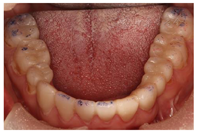

12、24、34、44牙缺失,12牙缺失牙间隙无,13牙与11牙建立邻接,24、34、44牙缺失牙间隙减少。咬合检查:上颌牙中线与面中线一致,下切牙中线右偏约1.5mm,11、13牙对刃,前牙部分开

,21、22、23、43牙与对侧牙无咬合接触,后牙有咬合,磨牙中性关系。余检查同术前(图8,图9,图10,图11)。